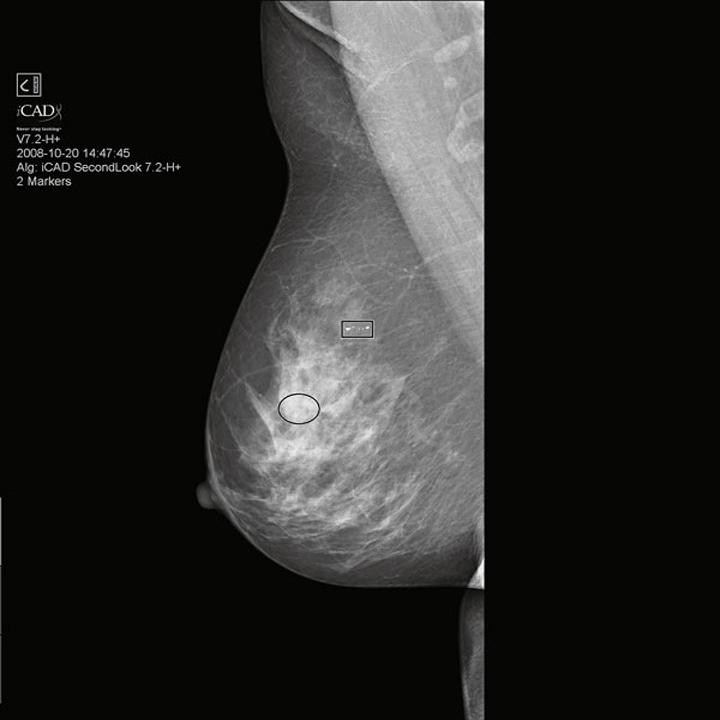

Whatever the individual situation, our innovations make screening and early diagnosis more reliable, efficient and comfortable than ever before - enabling early and therefore more effective therapeutic intervention.